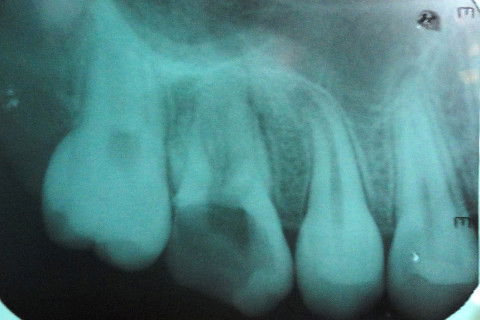

Aspecto Radiográfico Inicial

Aspecto Radiográfico após tratamento endodôntico concluído